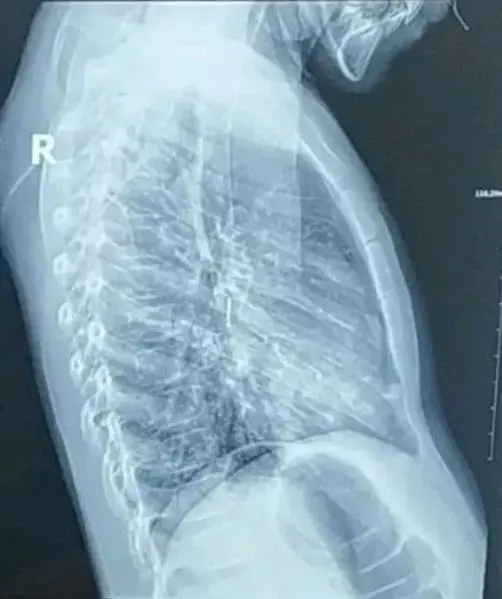

В Днепре врачи изъяли из бронхов 7-летнего ребенка постороннее тело.

По его словам, родители ребенка обратились к семейному врачу с жалобой на постоянный кашель у их ребенка. Впоследствии было выяснено, что ребенок вдохнул канцелярскую кнопку, попавшую ему в правый бронх.

Пациенту пришлось провести ригидную бронхоскопию. При удалении кнопки за ребенком наблюдали реаниматологи и хирурги.